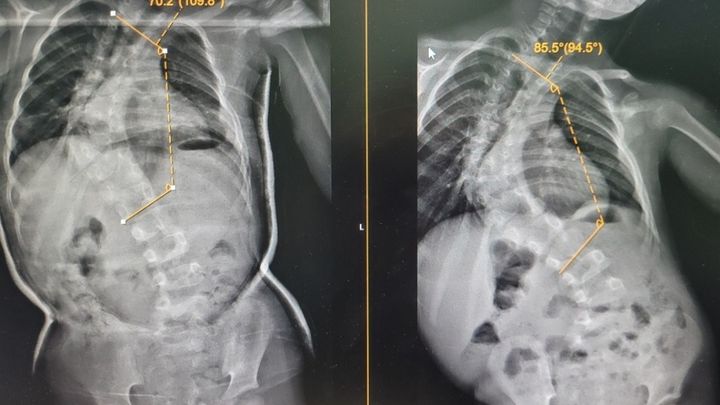

My little 6 year old daughter is having major spinal surgery on the 14th Feb. Violet suffers from serve scoliosis. She will be in hospital for up to two weeks.